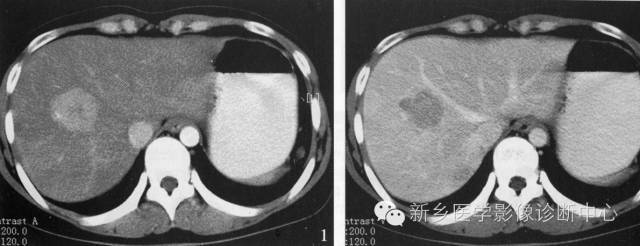

3、肝血管瘤

肝血管瘤在组织学上分为海绵状血管瘤、硬化性血管瘤、血管内皮细胞瘤和毛细血管瘤。是肝脏最常见的良性肿瘤。肝脏的血管瘤多数为海绵状血管瘤。多无临床症状。

病理表现:单发或多发,可位于肝包膜下,向外突出于肝表面,也可比较深在。肿瘤被覆结缔组织被膜,与周围肝组织分界清楚,由充满血液的血管囊腔构成,囊腔间有纤维性分隔。肿瘤可发生纤维化,钙化及血栓形成。

CT表现特点:病灶多为圆形或类圆形,边界清楚但无假包膜。平扫呈均匀低密度,增强扫描病灶边缘呈明显的不连续的结节状强化,强化区域进行性向中心扩展。延迟扫描病灶呈高密度充填。较大的病灶中心可见始终不充填。

血管瘤与其他富血供肿瘤的鉴别:①血管瘤的强化与血管相当。②血管瘤在延迟影像上呈持续强化。③血管瘤有周围结节样强化,其环内缘呈波浪状,而肝转移瘤其强化环内缘凹凸不平。④血管瘤增强后呈进行性持续性、向心性强化,无“周围洗脱”现象。